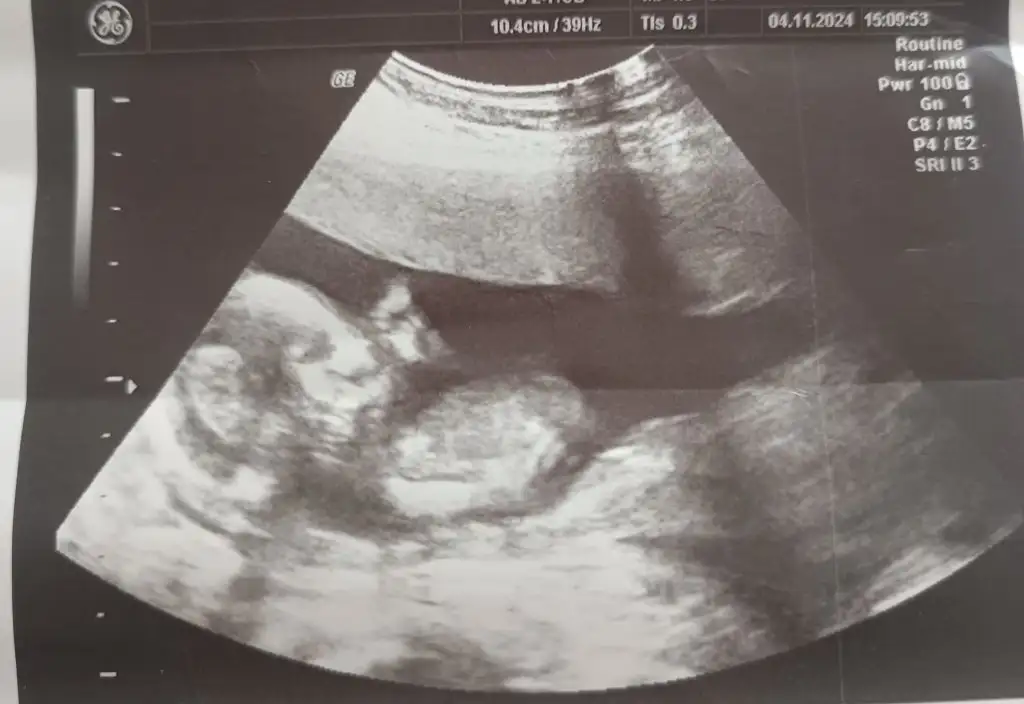

• IMG_20241105_134832.webp

IMG_20241105_134832.webp

23,9 KB · Görüntüleme: 92

• IMG_20241105_134810.webp

IMG_20241105_134810.webp

20 KB · Görüntüleme: 77

• IMG_20241105_134740.webp

IMG_20241105_134740.webp

23,2 KB · Görüntüleme: 74

Tahmin eder misiniz